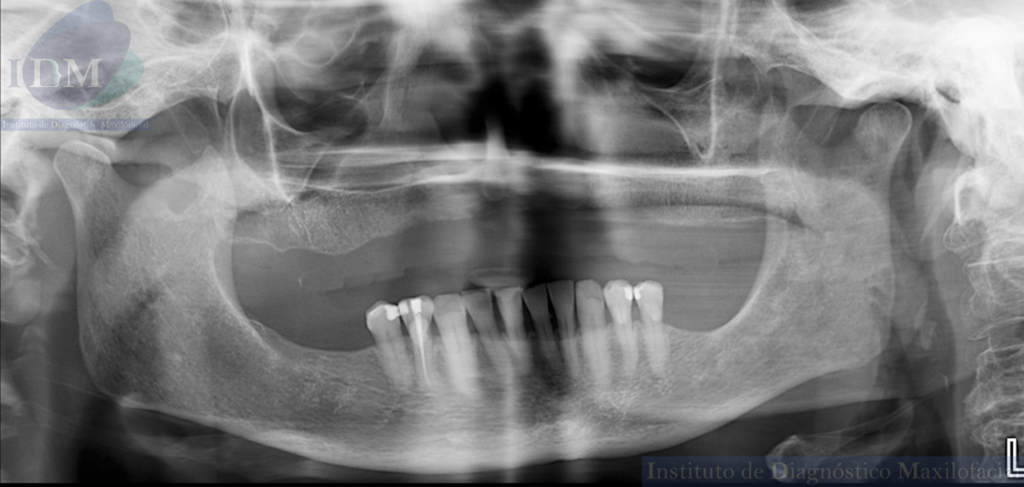

A la evaluación de la radiografía panorámica se observa paciente Edéntulo total del maxilar superior, piezas dentarias del maxilar inferiores con múltiples restauraciones coronarias, reabsorción ósea del proceso alveolar y la pieza 44 con obturación de conducto.

Radiografia Panorámica